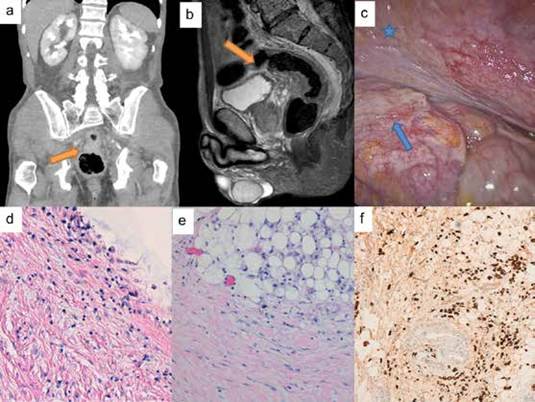

Mujer de 80 años, con estudios previos por diarrea y tenesmo rectal, al tacto rectal se encontró un engrosamiento rectal en la cara anterior, sin irregularidad mucosa. Se estudió mediante tomografía computarizada (TC) (figura 1a y 1b), con hallazgo de engrosamiento rectal ya sospechado y neoplasia gástrica, y colonoscopia donde se encontró una estenosis rectal extrínseca (figura 1c), secundaria al engrosamiento de recto que imposibilita el paso del endoscopio, sin hallazgos anatomopatológicos de malignidad sobre la mucosa. La gastroscopia encontró un adenocarcinoma gástrico pobremente diferenciado T3N2.

Se realizó laparoscopia exploratoria, hallando linitis plástica del estómago, sin datos de carcinomatosis peritoneal macroscópica. Se encontró engrosamiento preperitoneal del fondo de saco de Douglas (figura 1d y 1e), con compromiso subseroso por la cara anterior del recto, causando estenosis rectal secundaria. Se realizaron múltiples biopsias intraoperatorias peritoneales y de peritoneo pélvico, siendo todas negativas para malignidad. A pesar de sospechar la posibilidad de enfermedad diseminada, ante la ausencia de claras imágenes de implantes peritoneales, y de biopsias que confirmaran la carcinomatosis peritoneal, se realizó gastrectomía total abierta, linfadenectomía D2 y colostomía del sigmoide en la fosa iliaca izquierda.

La paciente presentó un posoperatorio favorable, siendo dada de alta al octavo día. La anatomía patológica definitiva informó adenocarcinoma gástrico difuso T4aN3a y M1 por positividad para afectación por carcinoma difuso encontrado en las biopsias del peritoneo de fondo de saco de Douglas con compromiso subseroso (figura 1f). La paciente vivió 12 meses con aceptable tolerancia oral y tránsito intestinal conservado, presentó recidiva peritoneal al octavo mes, sin recibir tratamiento adyuvante debido a su edad y comorbilidades.

Paciente masculino de 67 años, tratado por adenocarcinoma gástrico difuso T3N1 mediante quimioterapia perioperatoria con esquema EOX, gastrectomía total y linfadenectomía D2. Anatomía patológica con bordes libres y citología peritoneal negativa. El seguimiento mediante TC y gastroscopia cada 6 meses, resultó normal hasta el décimo sexto mes, cuando presentó tenesmo rectal y elevación de los marcadores tumorales. Al tacto rectal se encontró rugosidad en la cara anterior rectal, no dolorosa y de aspecto extrínseco. Se realizó TC y resonancia magnética nuclear (RMN), (figuras 2a y 2b), observando el engrosamiento circunferencial de las paredes del recto y del sigmoide distal, de aspecto congestivo, sin visualizar lesiones neoplásicas primarias de recto.

Se completó el estudio mediante colonoscopia y ultrasonografía endoscópica, encontrando un discreto engrosamiento de la submucosa e hiperecogenicidad a nivel de la grasa del meso rectal. Todas las biopsias endoscópicas fueron negativas, y se observó predominio del tejido conectivo, con ausencia de celularidad. Se realizó laparoscopia exploratoria, encontrando el engrosamiento del fondo del saco peritoneal, conocido como escudo de Blumer (figura 2c), sin hallazgos claros de carcinomatosis peritoneal macroscópica. Las biopsias quirúrgicas resultaron positivas para infiltración subserosa por carcinoma difuso (figura 2d, 2e y 2f) por lo que se realizó tratamiento paliativo mediante quimioterapia.